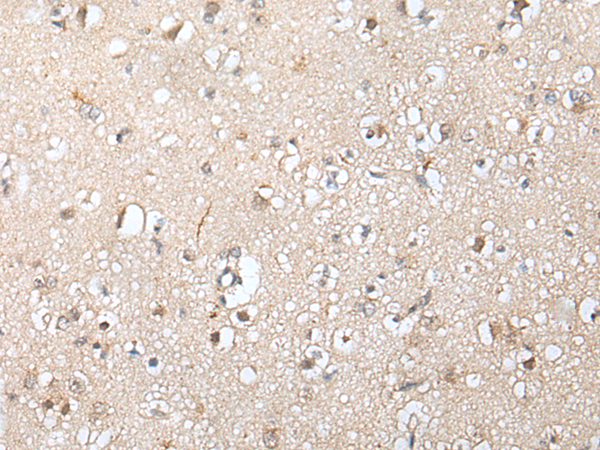

IHC positive control:

Human brain and human gastric cancer